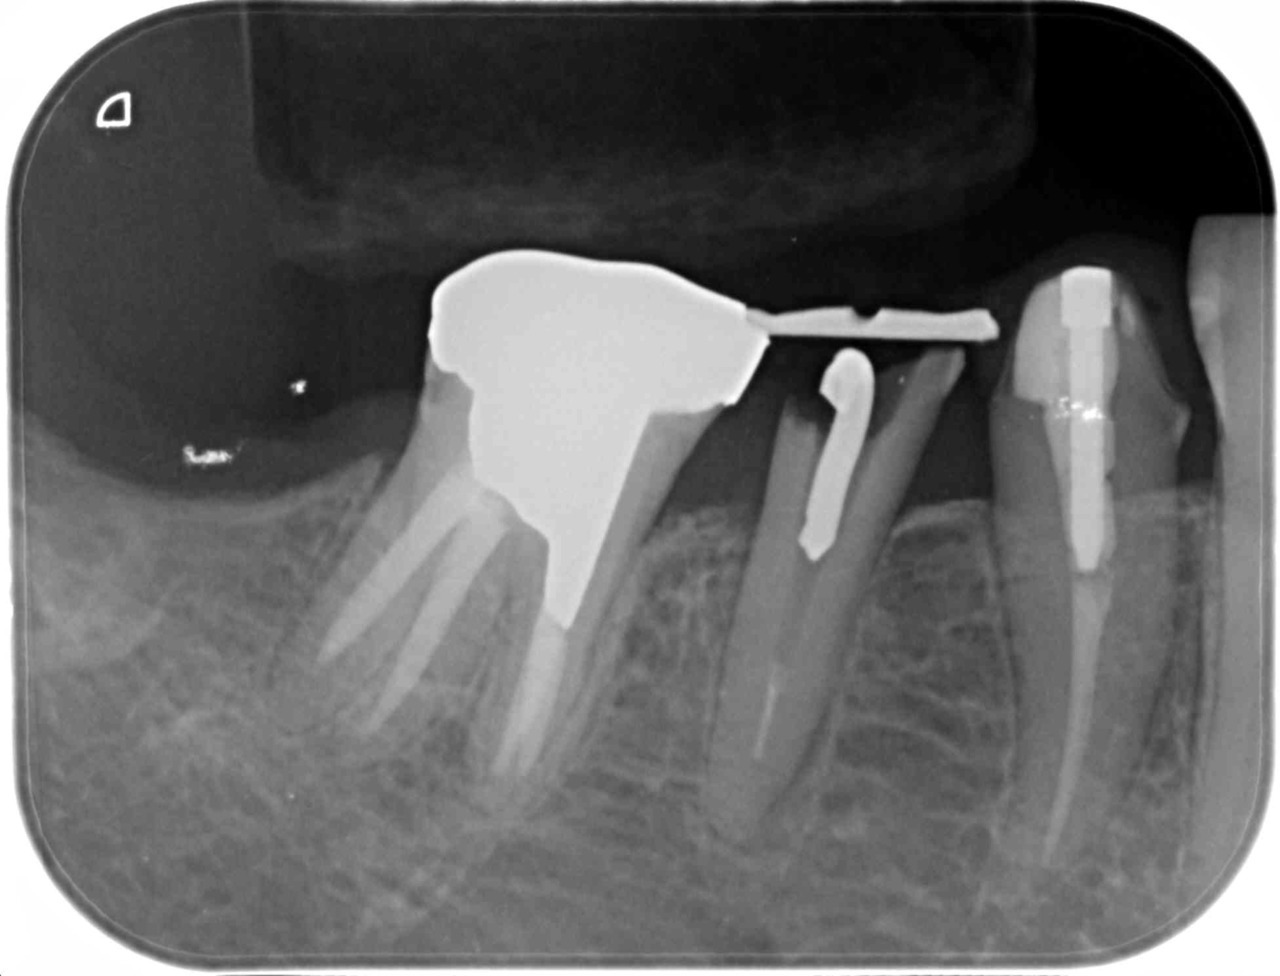

| R1 6/8 | 「代表的な治療例(むし歯 症例6)」を更新しました |

| R1 6/7 | 「代表的な治療例(移植・再植 症例2)」を更新しました |

歯を極力抜かない

保存する治療を重視

歯を極力抜かず治すために、私たちはMTM(部分矯正)と移植・再植を軸に治療を組み立てます。

大きなむし歯・歯周病・歯の破折など様々なシーンで活用している方法です。